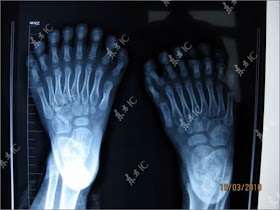

Inilah hasil Foto Rontgen Bocah berumur 6 tahun yang memiliki 15 Jari tangan dan 16 Jari kaki, dengan jumlah total 31 Jari yang ada ditubuhnya, menurut para ilmuwan, hal ini terjadi karna akibat dari mutasi Gen yang ada didalam tubuh bocah tersebut.